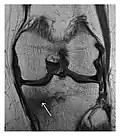

Proximal femoral fractures usually occur in osteoporotic patients, and their signs include subtle neck angulation, trabecular angulation, and subcapital impaction line. A frog-leg lateral view may be helpful if the greater trochanter is short enough. However, positioning can be difficult because of hip pain. In patients with strong suspicion of proximal femoral fracture and negative radiographs, MRI limited to coronal T1 W images and scintigraphy can be highly valuable (Figures 13 and 14). Such an option, with limited examination time, is cost-effective and allows reliable exclusion or confirmation of the diagnosis, preventing an unnecessary stay at the hospital or delayed treatment. Moreover, MRI helps to detect soft tissue abnormalities which are more frequently seen in femoral, acetabular, and pubic injuries than sacral lesions. Concomitant fractures are also frequently seen in typical pelvic sites.[1]

-

a -

b

Figure 14: Subcapital insufficiency fracture in a 55-year-old man with a left hip pain without a history of trauma. Anteroposterior and Lauenstein view radiographs centered on the left hip do not show an obvious fracture line, but mild acetabular osteophytosis was noted consistent with hip osteoarthritis (not shown). (a) Coronal T1-weighted MRI shows a linear low-signal band through the femoral neck corresponding to a fracture line (arrowheads). (b) Bone scintigraphy shows focal uptake (arrow) corresponding to the fracture.[1]